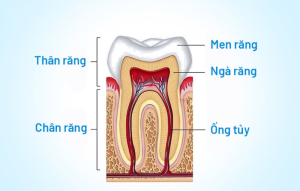

Hàn trám răng là một phương pháp nha khoa xâm lấn tối thiểu được sử dụng để khôi phục hình dáng và chức năng của răng bị tổn thương như răng bị sâu, mẻ hoặc gãy. Trong quá trình hàn trám, nha sĩ sẽ lấp đầy các khuyết hổng trên răng bằng vật liệu trám có màu sắc tương đồng với răng thật.

- Sâu răng: Khi sâu răng gây ra lỗ hổng, hàn trám giúp lấp đầy khoảng trống này và ngăn chặn sự phát triển của sâu răng thêm.

- Răng bị mẻ hoặc gãy: Nếu răng bị mẻ hoặc gãy, hàn trám có thể phục hồi hình dáng răng và bảo vệ phần còn lại của răng.

- Sửa chữa răng sau khi điều trị tủy: Sau khi điều trị tủy, răng cần được phục hồi bằng vật liệu trám để bảo vệ và duy trì chức năng.

Trong trường hợp răng sâu nặng, mẻ lớn ảnh hưởng đến tủy thì bác sĩ sẽ tiến hành bảo vệ che tủy trực tiếp hoặc gián tiếp bằng vật liệu tương hợp sinh học MTA. Trường hợp nặng hơn khi tủy bị viêm thì bác sĩ sẽ tiến hành điều trị tủy. Tất cả các thủ thuật đều có gây tê nên khách hàng sẽ không cảm thấy đau.